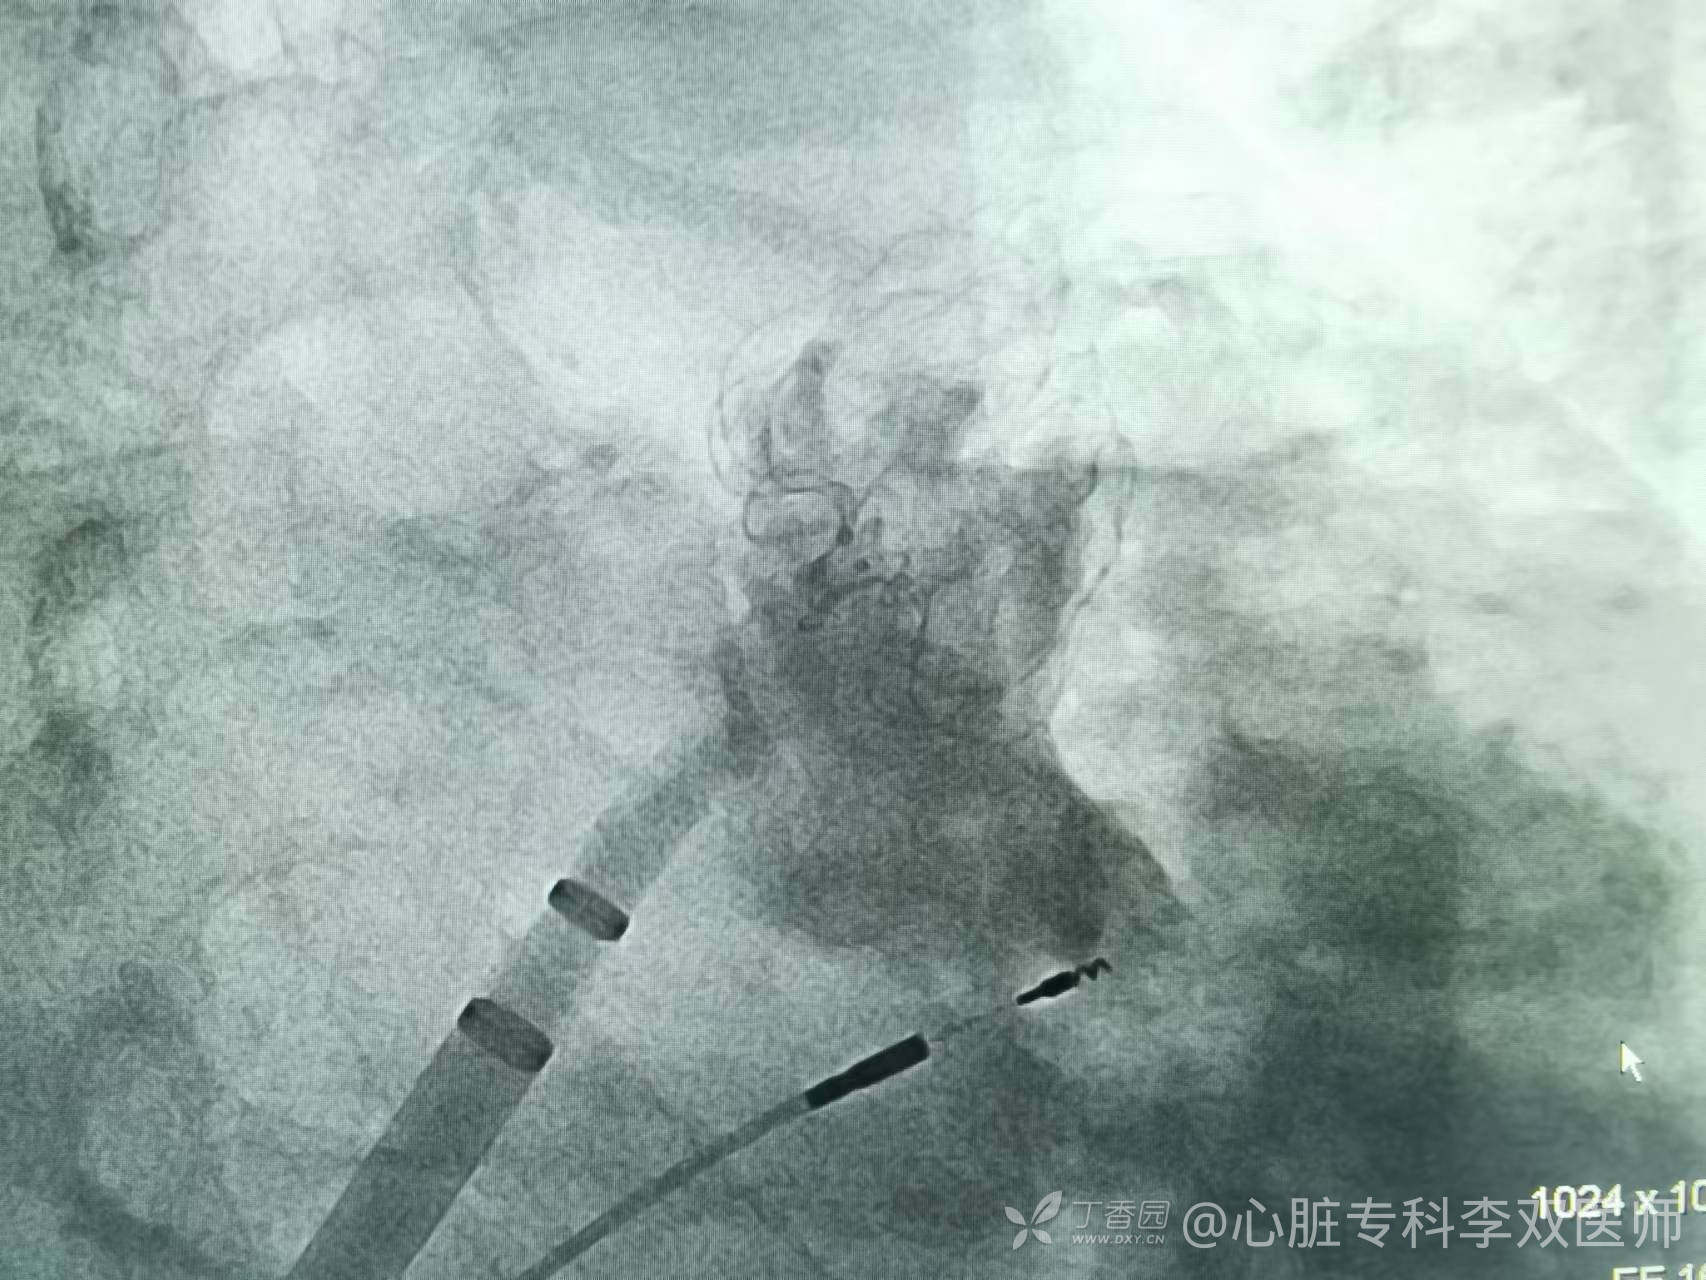

反复脑梗的瘦老先生,房颤消融过三次均复发,伴病窦综合征,一周前植入过双腔起搏器。这次家属要求解决脑梗的问题,术前cta提示心耳口小肚子大足够深,难度小。采用极简式,无需麻醉,手术的难点主要是避开起搏导线完成房间隔穿刺,体位选择很重要。保证一次穿刺成功,一次封堵术释放成功,半小时结束手术。